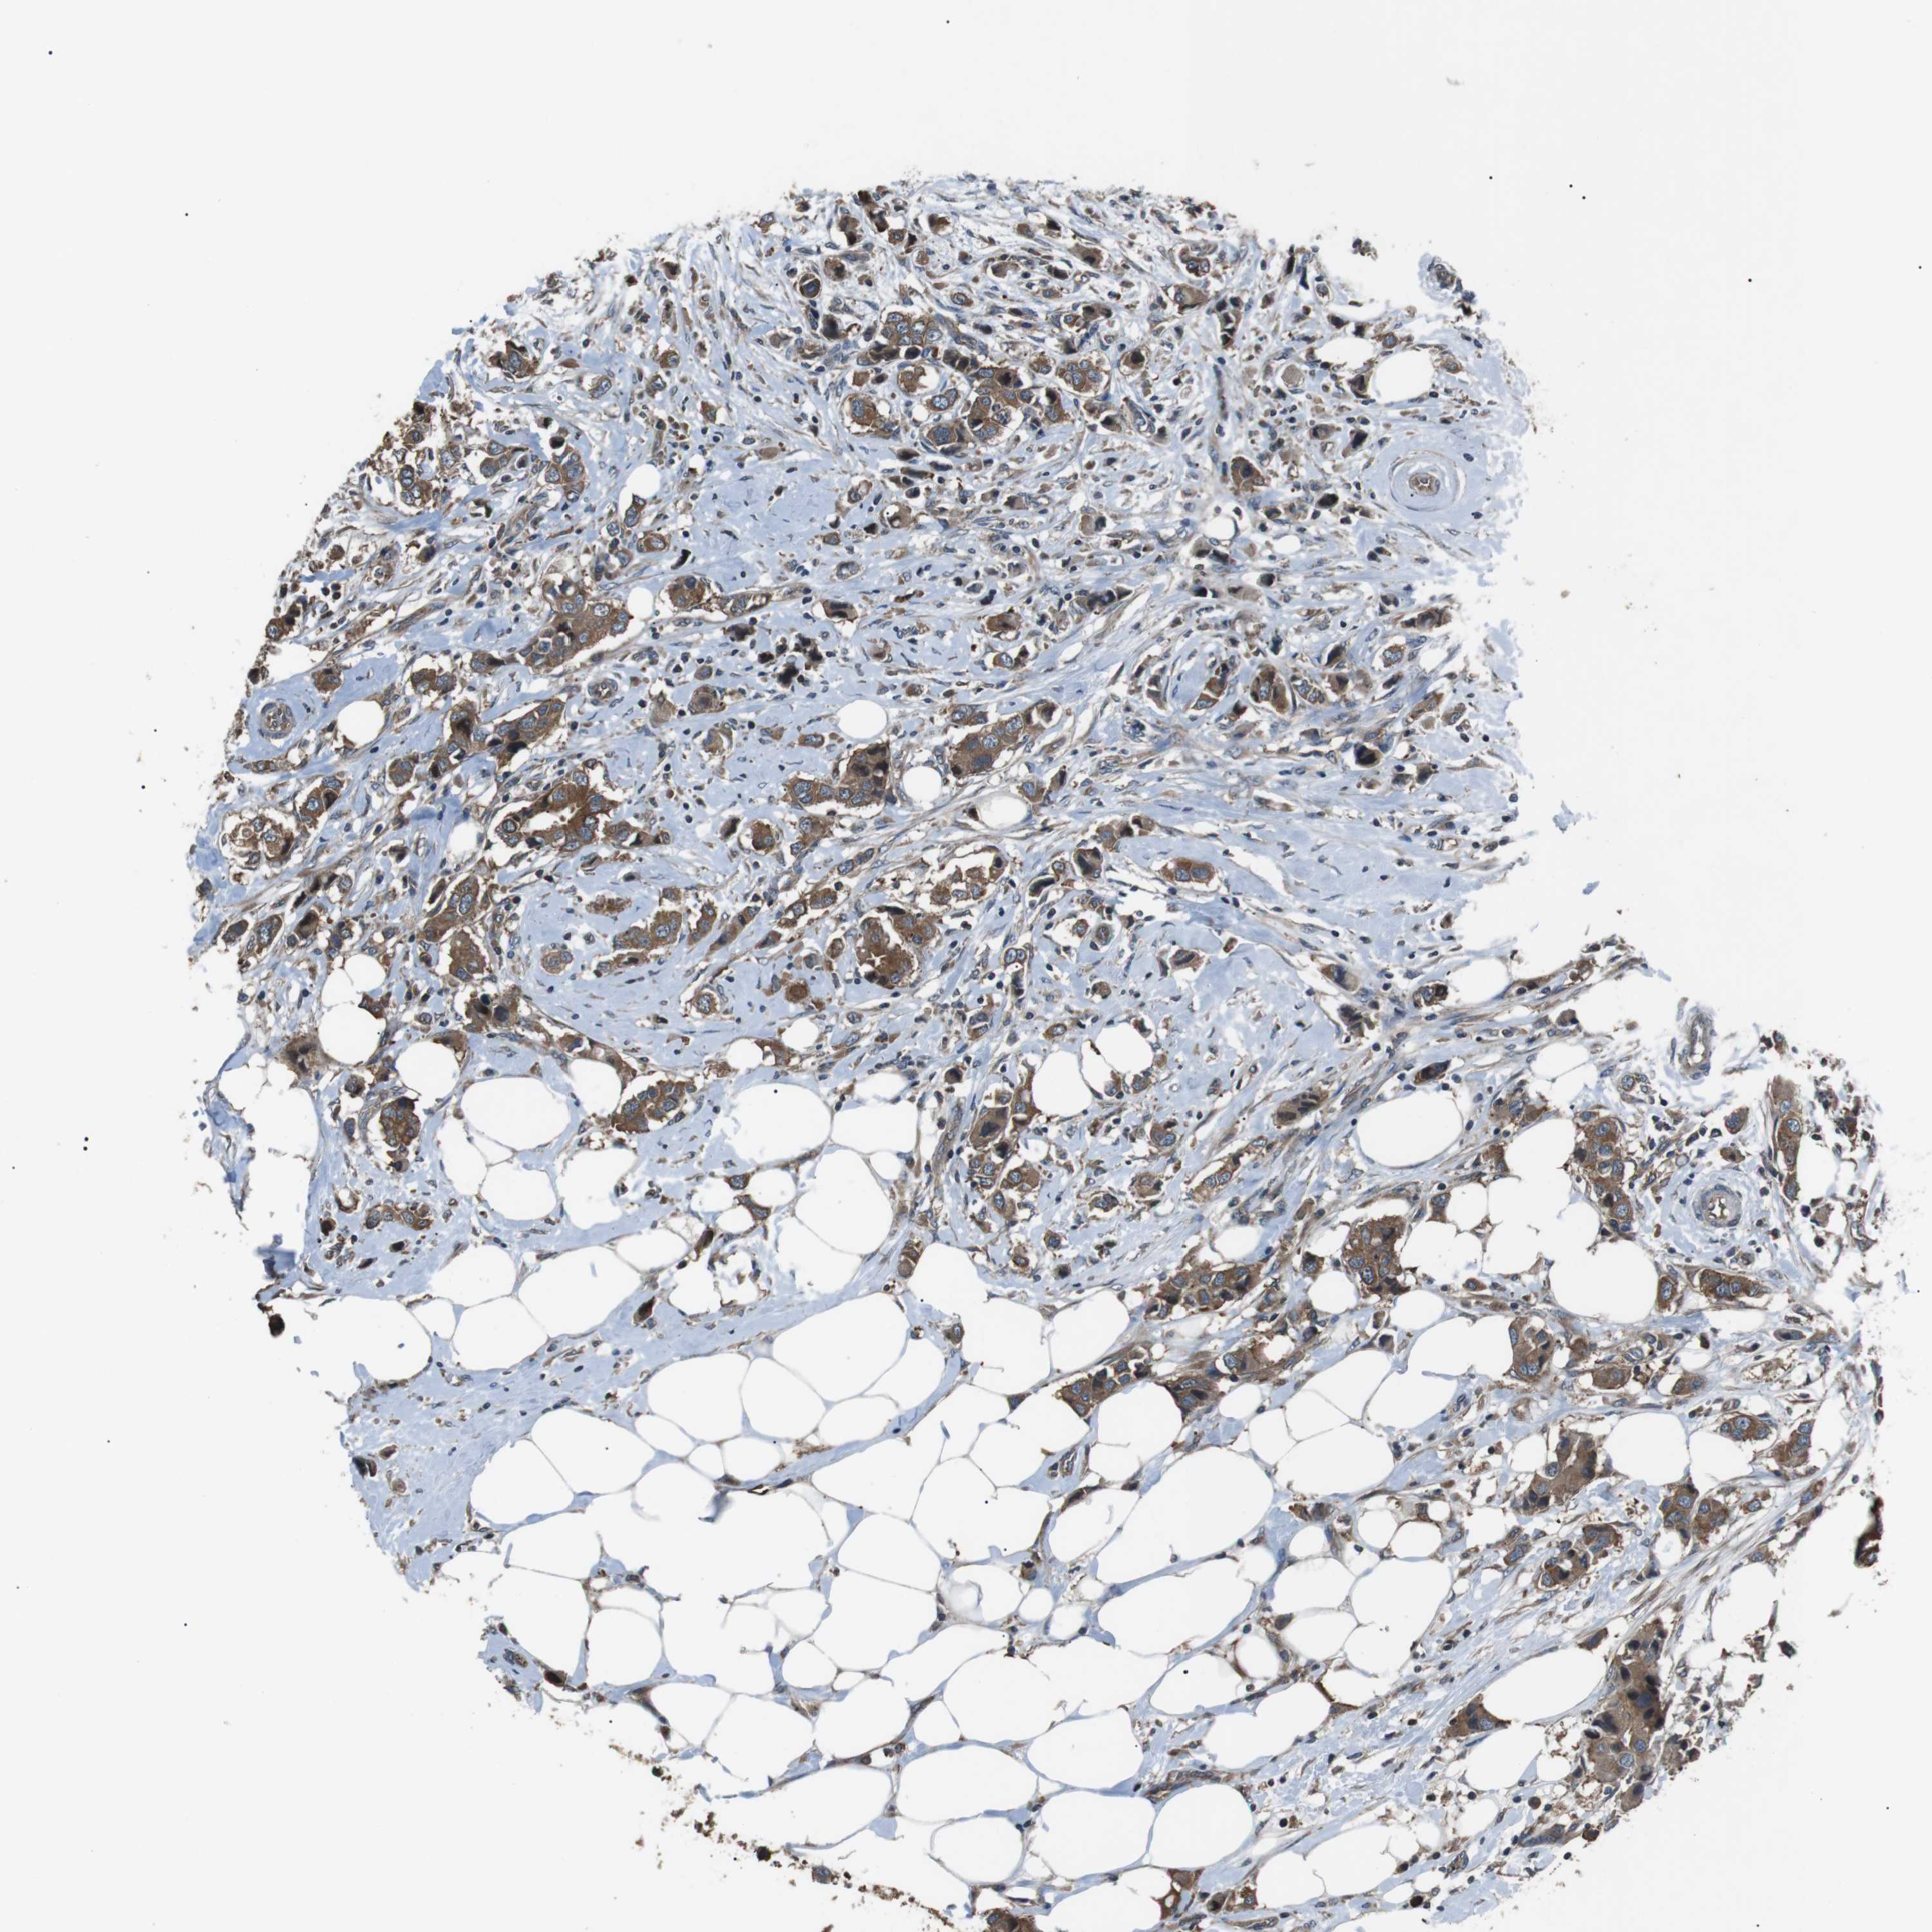

CANCER BREAST CANCER Show tissue menu

BRCA TCGA BRCA VALIDATION PROTEIN EXPRESSION